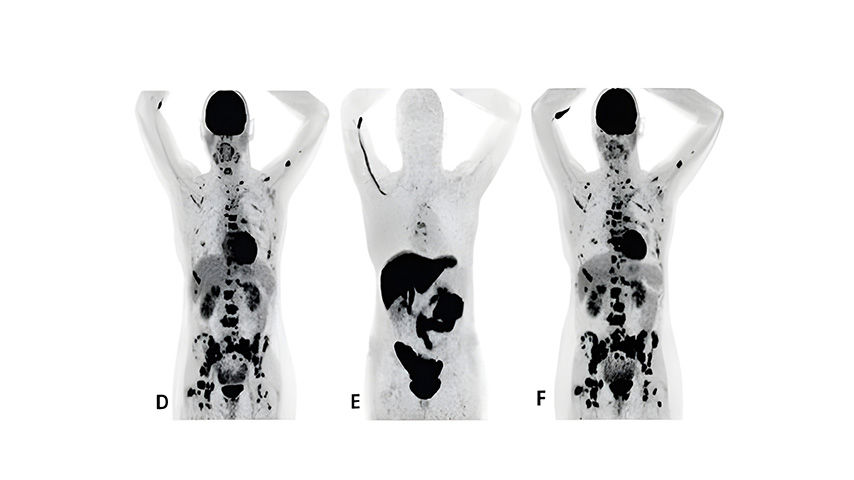

F18 fluoroestradiol and FDG PET images in a MBC treatment responder and non-responder*†⁶

Patient 2

(anterior/superior) did not respond to treatment with an AI and a CDK 4/6 inhibitor*6

†Upper row responder: Baseline FDG PET (A) showed pathological uptake in axillary lymph nodes (right side) and in nearly all vertebrae and pelvic bones. Image B showed the baseline F18 fluoroestradiol PET with pathological ER expression in the axial skeleton (including vertebrae, pelvic bones, proximal humeri and femora) and in axillary lymph nodes (right side). After 8 weeks, the FDG PET (C) showed almost complete metabolic response (just some slightly elevated uptake in the axillary lymph nodes). The patient had been on treatment for more than 70 weeks. Lower row non-responder: Baseline FDG PET (D) showed pathological uptake in multiple skeletal lesions. Image E showed the baseline F18 fluoroestradiol PET with only some increased ER expression in thoracic vertebrae. After 8 weeks, the FDG PET (F) showed no metabolic response, even some increase in the pathologic uptake in the multiple skeletal lesions6.

Images from a prospective, single center, feasibility study that aimed to explore whether baseline F18 fluoroestradiol PET discordance and F18 fluoroestradiol uptake were correlated with outcome and response to concomitant treatment with an AI and a CDK 4/6 inhibitor. Thirty patients with ER+ MBC were included in the study, including 87% who received at least one previous line of ET in the metastatic setting6.

*The F18 fluoroestradiol administered in this study was not equivalent to the FDA-approved formulation of Cerianna.